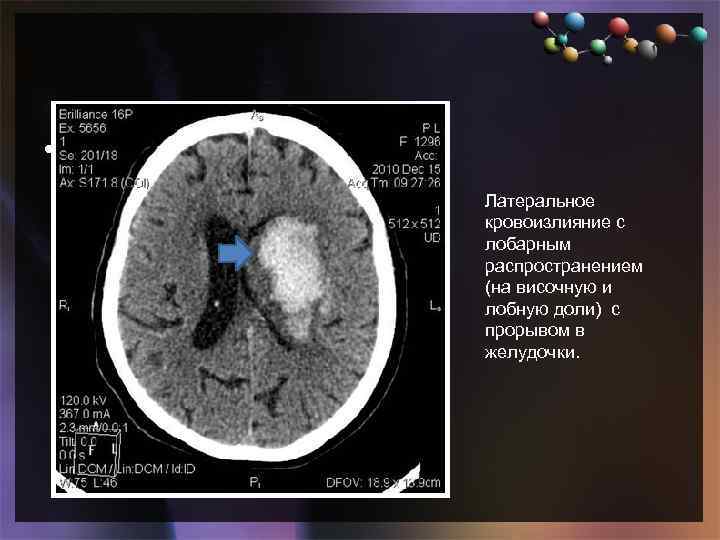

• Подзаголовок слайда Латеральное кровоизлияние с лобарным распространением (на височную и лобную доли) с прорывом в желудочки.

• Подзаголовок слайда Латеральное кровоизлияние с лобарным распространением (на височную и лобную доли) с прорывом в желудочки.